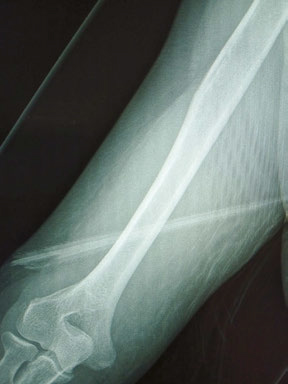

A CT scan showed the barb was positioned against the brachial artery but fortunately had not pierced it. It was then surgically removed.

“The nerves are still intact and the arteries are intact, so it’ll all heal, I’ll just have a bit of a scar,” Ms Bennett said.